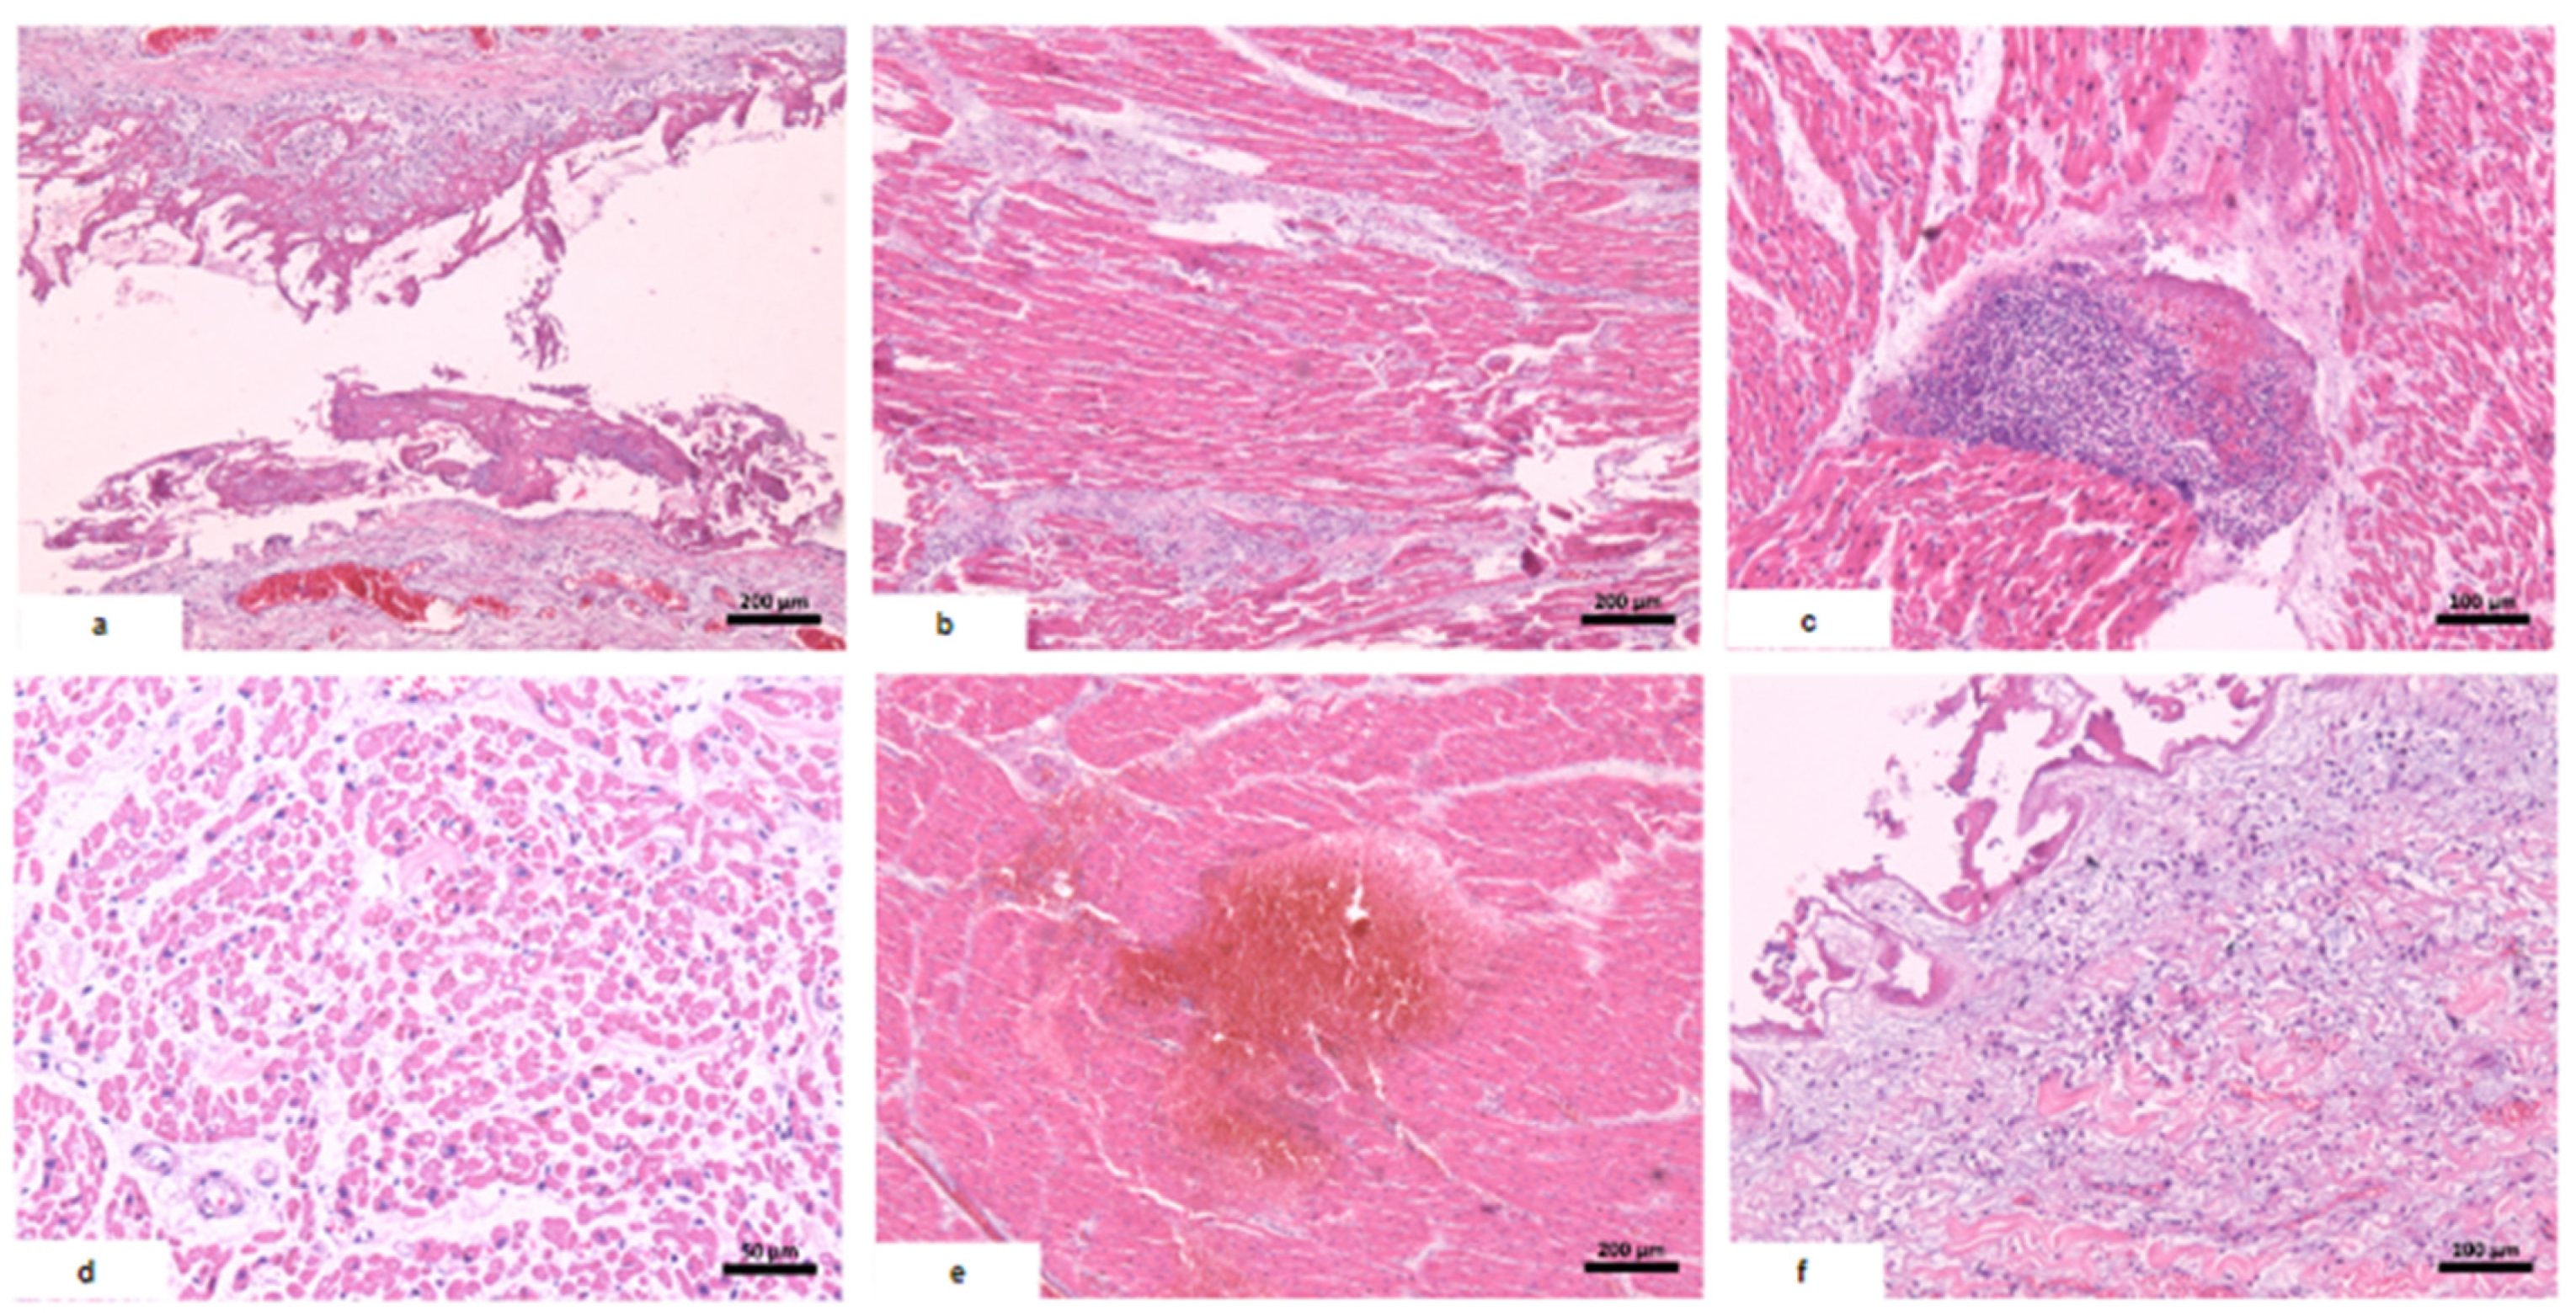

| Macroscopic findings | Edema and tonsil herniation. | Fibrinous perimyocarditis with hemorrhage. Valves unchanged | Edema and congestion. | Moderate steatosis hemorrhagic appearance | Signs of shock. |

| Microscopic findings | Tissue edema. Reactive gliosis. Vascular thromboembolism. | Pericardium: intense deposition of fibrin, red blood cells, and inflammatory cells. Myocardium: interfascicular edema, coagulative myocyte necrosis. Hemorrhage and inflammatory infiltrate rich in macrophages and t-cells. Aschoff’s nodules and/or Anitschkow’s cells: not observed. Endocardium: slight loose fibrosis and inflammatory infiltrate. | Parenchymal hemorrhage. Vascular thromboembolism. Inflammatory infiltrate of lymphocytes, neutrophils, and xanthomatous macrophages. | Hemorrhagic necrosis. Vascular thromboembolism. Microvesicular steatosis. | Acute tubular necrosis. |